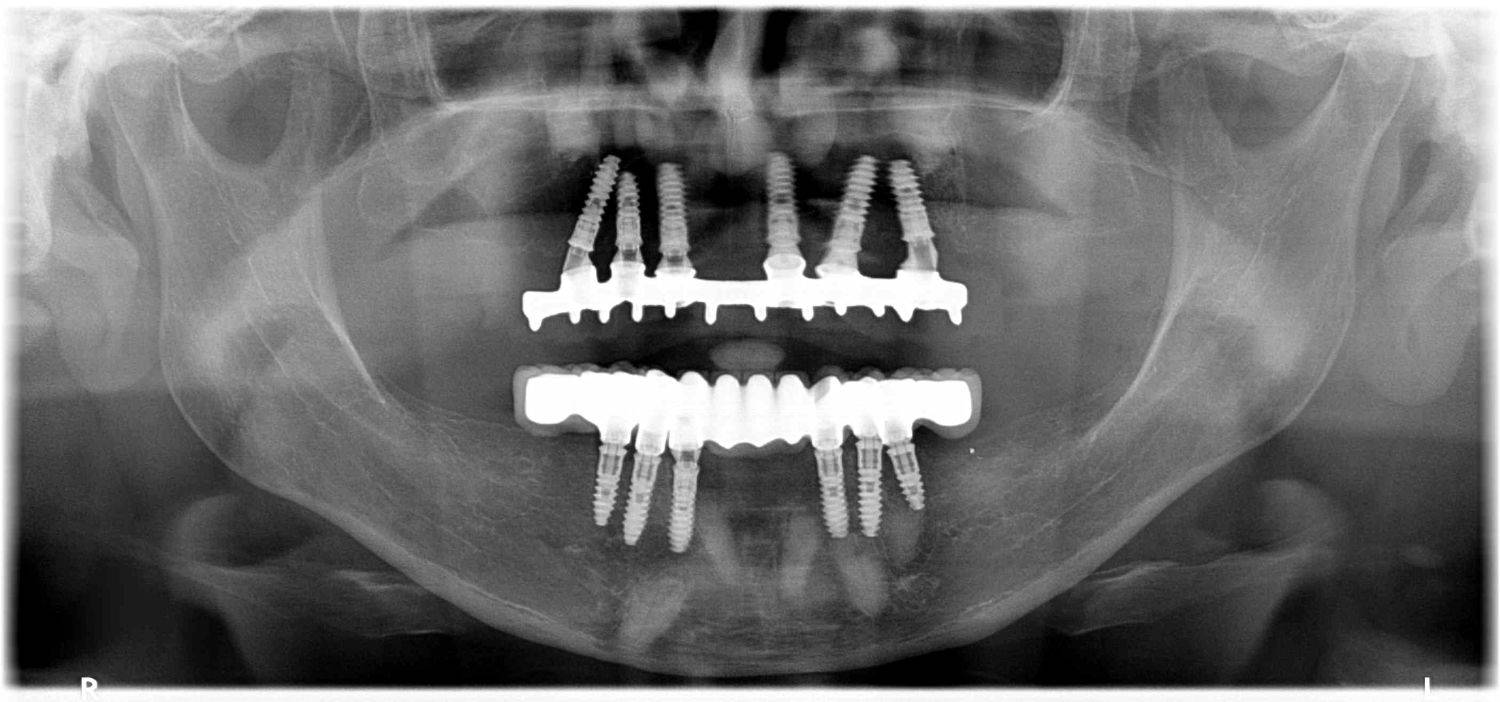

1. eset

A páciens fogágybetegség miatt érkezett hozzánk. A felső fogak menthetetlen állapotban voltak. All on 6 megoldásként a felső fogak eltávolításakor 6 implantátum került beültetésre és a páciens azonnal egy fix ideiglenes hidat kapott. 4 hónapos gyógyulási idő után készült el a felső fémkerámia leplezésű körhíd.